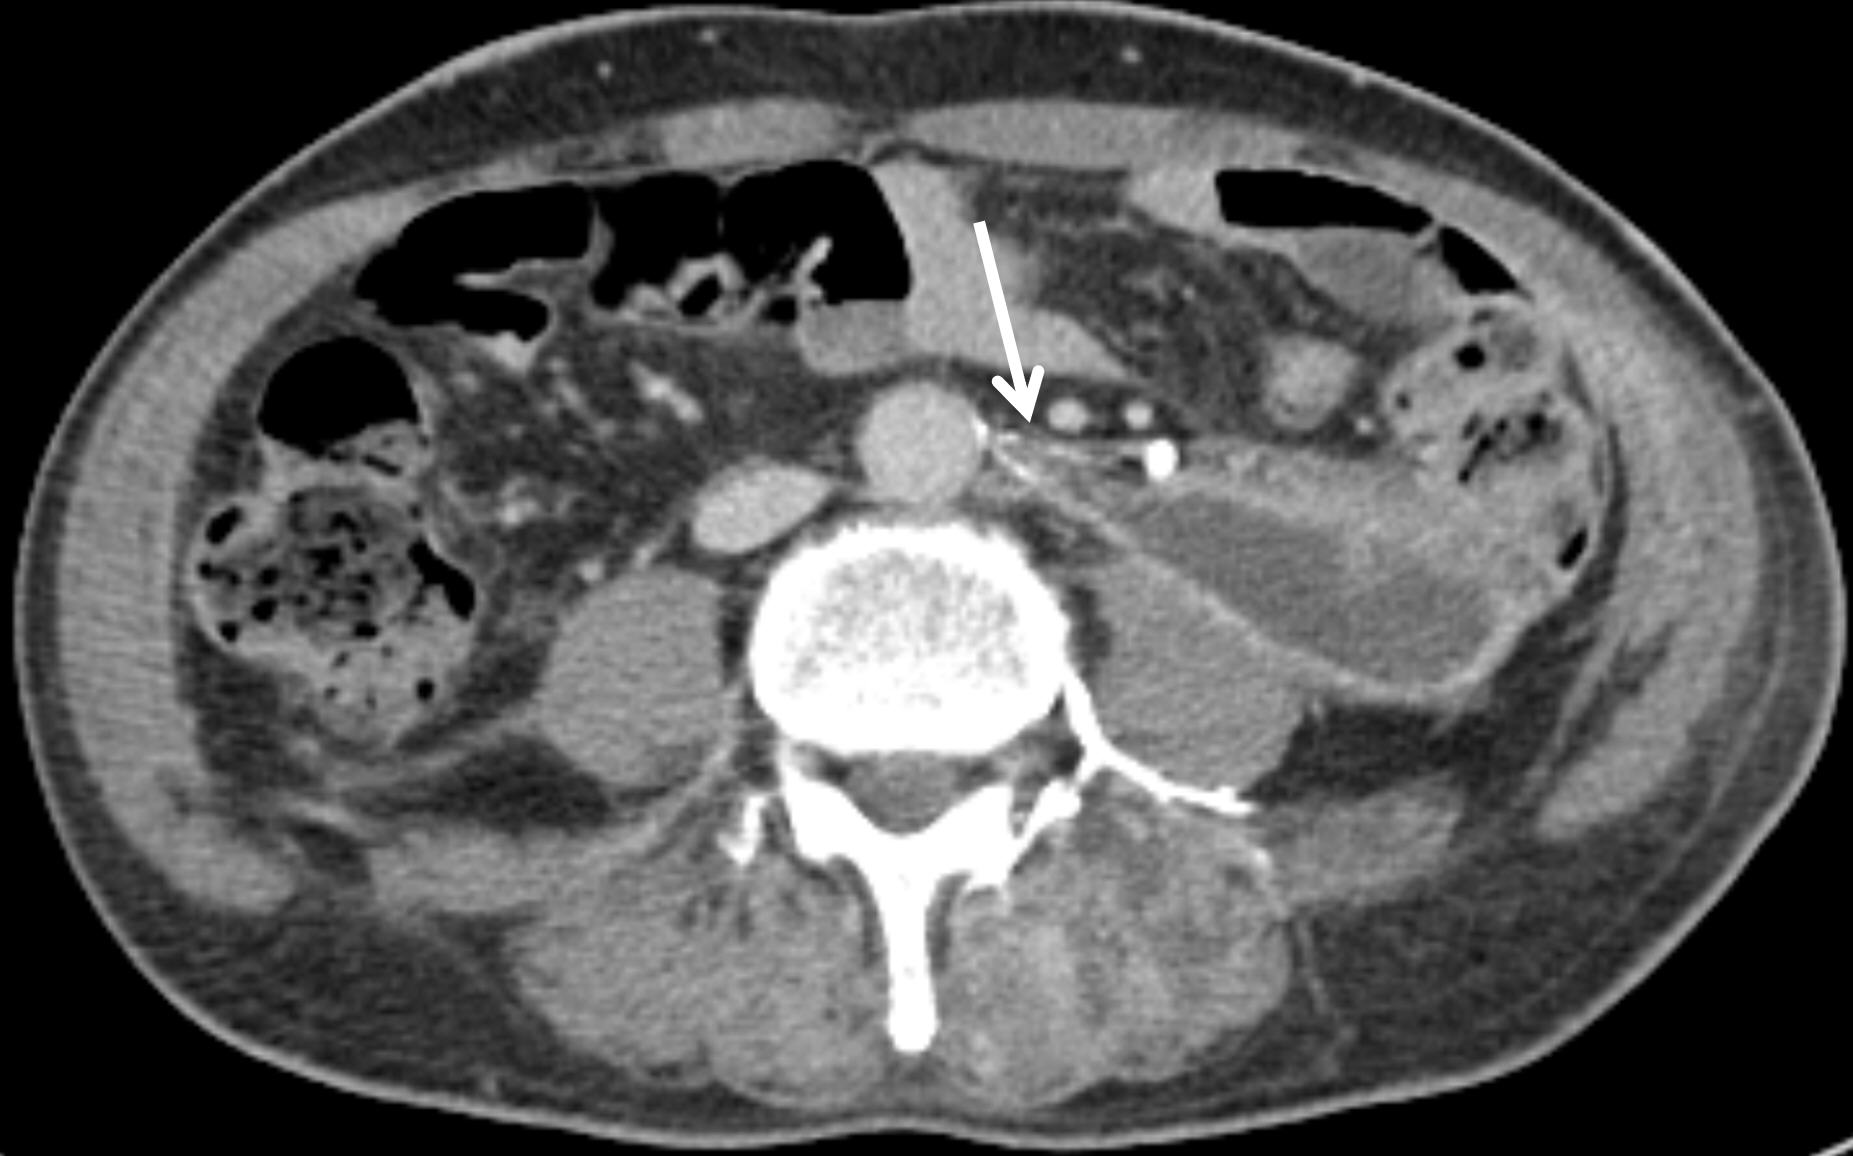

Axial cone-beam CT images revealed a thin artery arising at the 12 o’clock position from the infrarenal aorta, which coursed leftward toward the left ureter, made an L-shaped bend, and descended, with active bleeding observed (

Fig. 2). Based on these findings, selective catheterization of this artery was achieved using the 5-Fr diagnostic catheter (RH; Jungsung Medical, Seoul, Korea) and a 1.5-Fr microcatheter (Veloute Ultra, Asahi Intecc, Nagoya, Japan). Embolization was then performed using a 1:4 mixture of NBCA and ethiodized oil.

Fig. 2.Axial and coronal cone-beam CT images as well as angiographic image, obtained during the procedure, demonstrate a bleeding left ureteric artery (arrows) originating from the abdominal aorta in the 12 o’clock direction and coursing posterolaterally to the left before sharply angling into an L-shaped configuration.